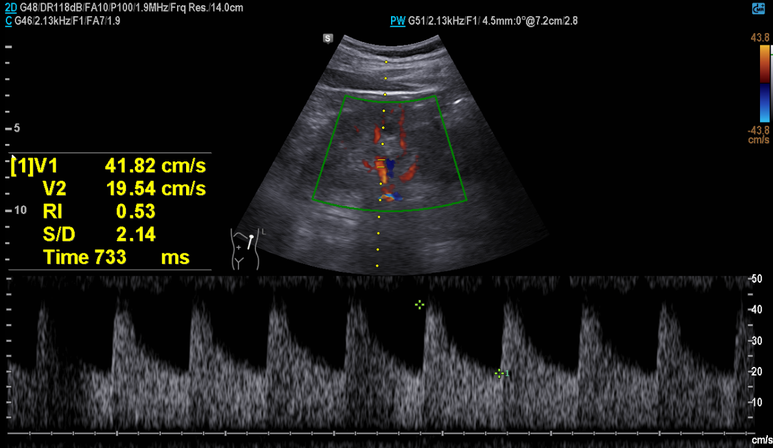

부신 우연종은 없었으며 RI는 정상 범위로 신동맥 협착 배제

부신 우연종은 없었으며 RI는 정상 범위의 상한선 소견, 이외 중등도의 지방간 소견